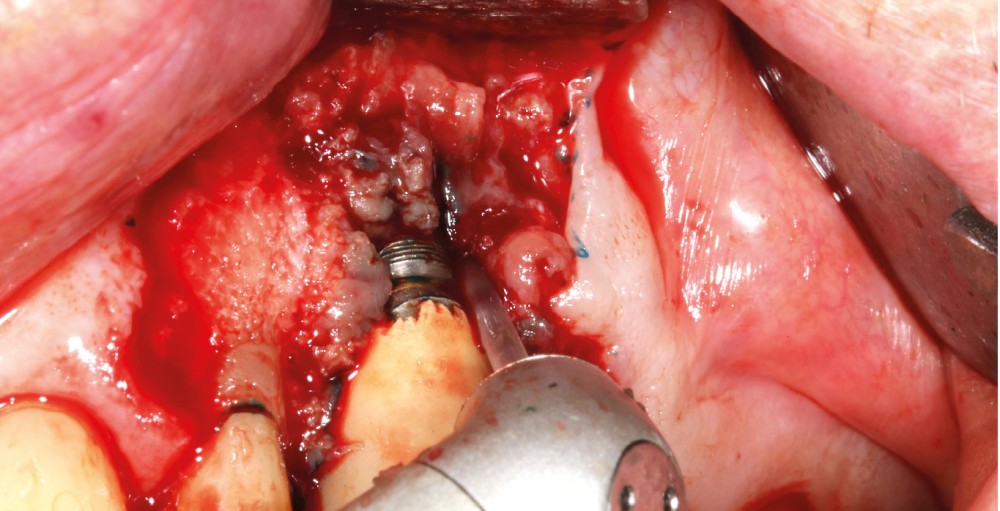

Le patient

- 70 ans

- Pas d’antécédents médicaux

- Ne fume pas

- Hygiène correcte

L’implant

- Site 23

- Mis en place il y a 12 ans

- Parmi ces longueurs d’onde, deux lasers (Er-YAG et Diode) sont intéressants dans le traitement de la péri-implantite :

– Le laser Er-YAG, utilisé pour le nettoyage, est un laser avec un milieu actif composé d’yttrium, d’aluminium et de grenat dopé à l’erbium. Avec une longueur d’onde de 2 940 nm situé dans l’infrarouge, le laser Er-YAG est un laser à haute énergie, dont la lumière est absorbée dans l’eau et dans l’hydroxyapatite et qui ne pénètre pas profondément. Ceci permet de couper des tissus mous et des tissus durs, mais également de désorganiser le biofilm bactérie.

C’est un laser idéal pour le traitement chirurgical des péri-implantites. Il permet l’élimination du tissu de granulation à la surface de l’implant et de l’os ainsi qu’une décontamination mécanique par effet photoablatif.– Le laser Diode, utilisé pour la décontamination…